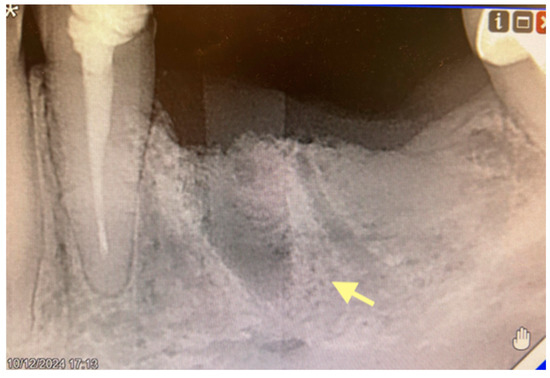

Figure 2.

Initial signs of osteonecrosis of the lower jaw in the area of the tooth 44 alveola (12 October 2024).

According to the classification of osteonecrosis of the jaws, the patient had stage I. Despite antibacterial therapy, an intraoral fistula formed. Therefore, in February 2025, an operation was performed (sequestrectomy with subsequent A-PRF placement).